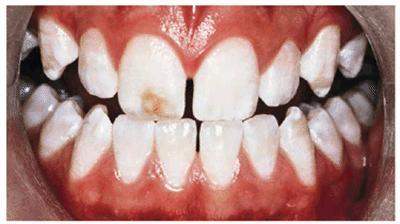

Does a brown spot on tooth mean cavity?

Brown spots on teeth can be an early warning sign of cavities, which require a dentist to fix. They may be accompanied by symptoms such as tooth pain, sensitivity, or bad breath. If tooth decay becomes severe, it may lead to gingivitis.

Tooth Decay and Tartar Brown spots, patches or lines on your teeth could be a sign of poor oral health. Tooth decay and cavities can look like brown stains, and when plaque hardens, it forms a yellow or brown substance called tartar, which lies along the gum line.

What Colour is tooth decay?

Generally speaking, a dental cavity (also called tooth decay) can range in color from white to brown and eventually black as the cavity continues to grow.

What do pre cavities look like?

While it is usually difficult to see a cavity in its beginning stages, some cavities start with a whitish or chalky appearance on the enamel of your tooth. More serious cases can have a discolored brown or black color. However, most often there are no distinguishable red alerts.

How can you tell if its a cavity or stain?

A cavity presents itself with a brown, black or gray spot on your tooth. It is a perfect way on how to tell if you have a cavity. A stain, on the other hand, is a discoloration caused by drinks and food. A stain is not sticky.

Is it a stain or a cavity?

If an entire tooth (or multiple teeth) appears discolored, then it's likely a stain. However, if you notice a small spot of discoloration on your tooth, then it's very likely a cavity. In addition, cavities appear dark brown or black.

What are the spots on my teeth?

Spots of brown discoloration on the teeth are very common. People can often prevent or eliminate them by making certain lifestyle changes or seeking dental treatment. These spots can vary in color from yellowish-brown to black-brown. The shape and size can vary.